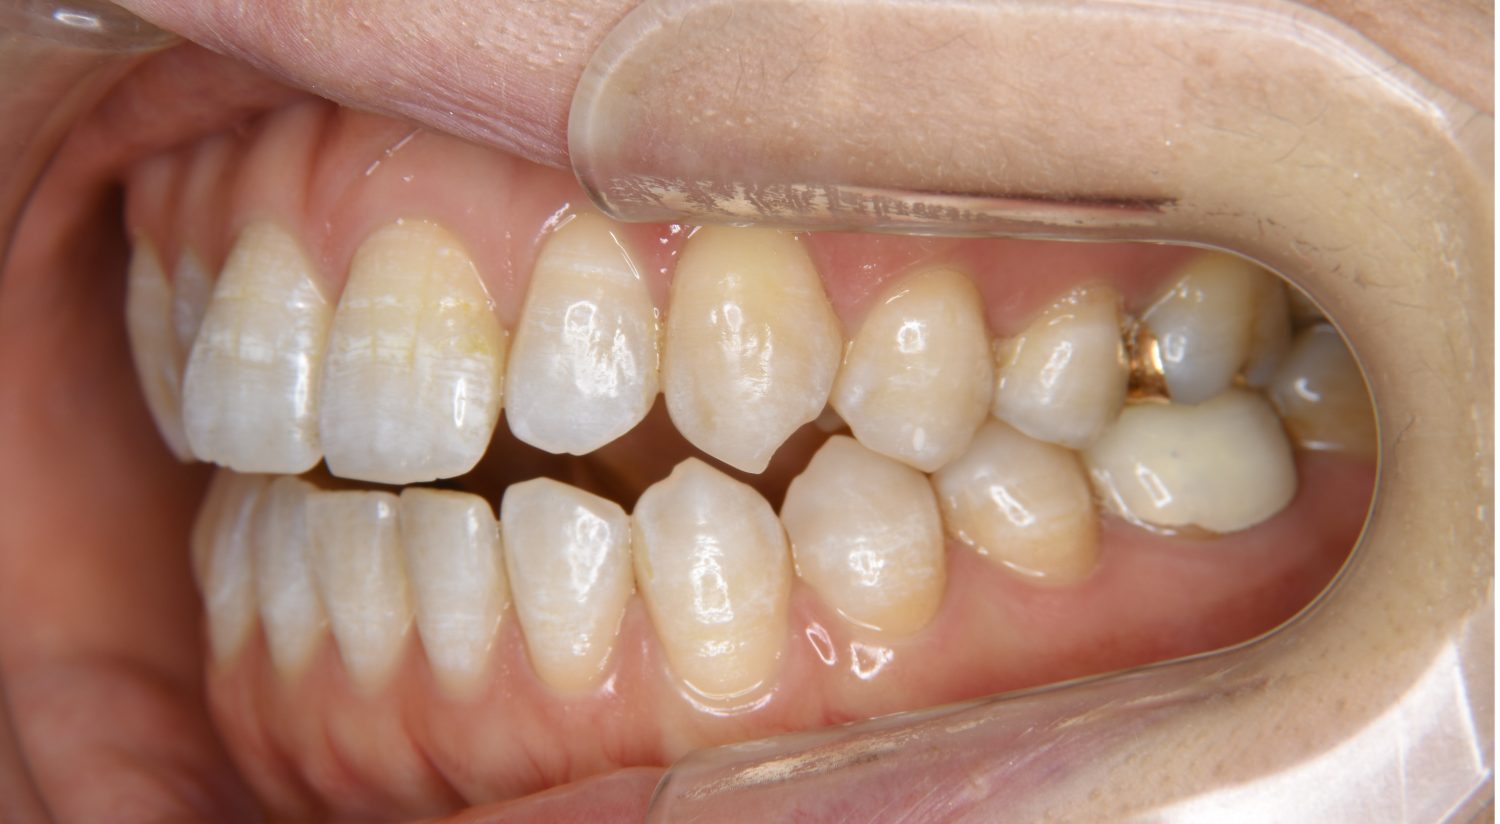

Before

主訴

前歯が開いているのが気になる。

治療内容

上リンガルブラケット(舌側装置)、下ラビアルブラケット(唇側装置)に矯正用アンカースクリューを併用し非抜歯で治療を行いました。

治療費

1,200,000 円(税込)

治療期間

33ヶ月

通院回数

34回

想定されたリスク

※歯根吸収、歯肉退縮、歯髄壊死、顎関節症状

上下の前歯が開いており前歯では全く噛めていない状態でした。臼歯の圧下を行うことで前歯でも咬合できるようになり機能面のみでなく審美面も著しく改善しました。